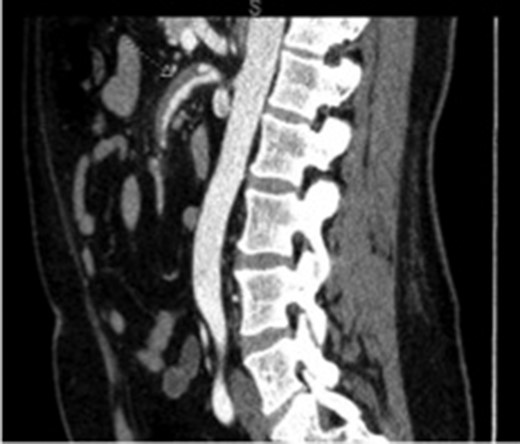

The patient was a 49-year-old male with history of hypertension presenting for evaluation for sudden onset of bilateral lower quadrant abdominal pain, nausea, emesis and non-bloody diarrhea starting 4 h prior to presentation. The patient denied prior abdominal surgeries, tobacco or illicit drug use. His history included hospitalization a year earlier for painless rectal bleeding, concerning for ischemic colitis, which was managed non-operatively. Current medications included Aspirin 81 mg and Valsartan-HCTZ. Physical exam revealed only mild left lower quadrant tenderness, and the labs values were quite unremarkable. A CT scan of the abdomen and pelvis with intravenous contrast demonstrated a thrombosed dissection, originating 2 cm from the ostium of the SMA with extension into the second and third order branches (Figs 1 and 2).

Initial imaging showing a thrombosed dissection, originating 2 cm from the ostium of the SMA with extension into the second and third order branches.